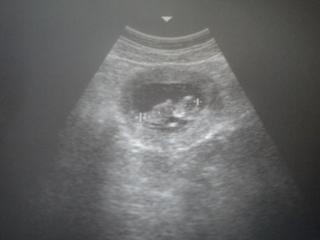

v piatok som bola aj na kontrole a aj na sone, doktorka uz videla pohlavie, ale na 100% to este nechcela potvrdit. uz mame 52mm a sme v 12+2 tt. vsetko je ok, zobrala mi krv, a mala by som konecne aj nieco pribrat .

@shilou fiha, no už ma tvoj drobec dosť veľa cm.. to bude určite marcovčiatko 😉 😉